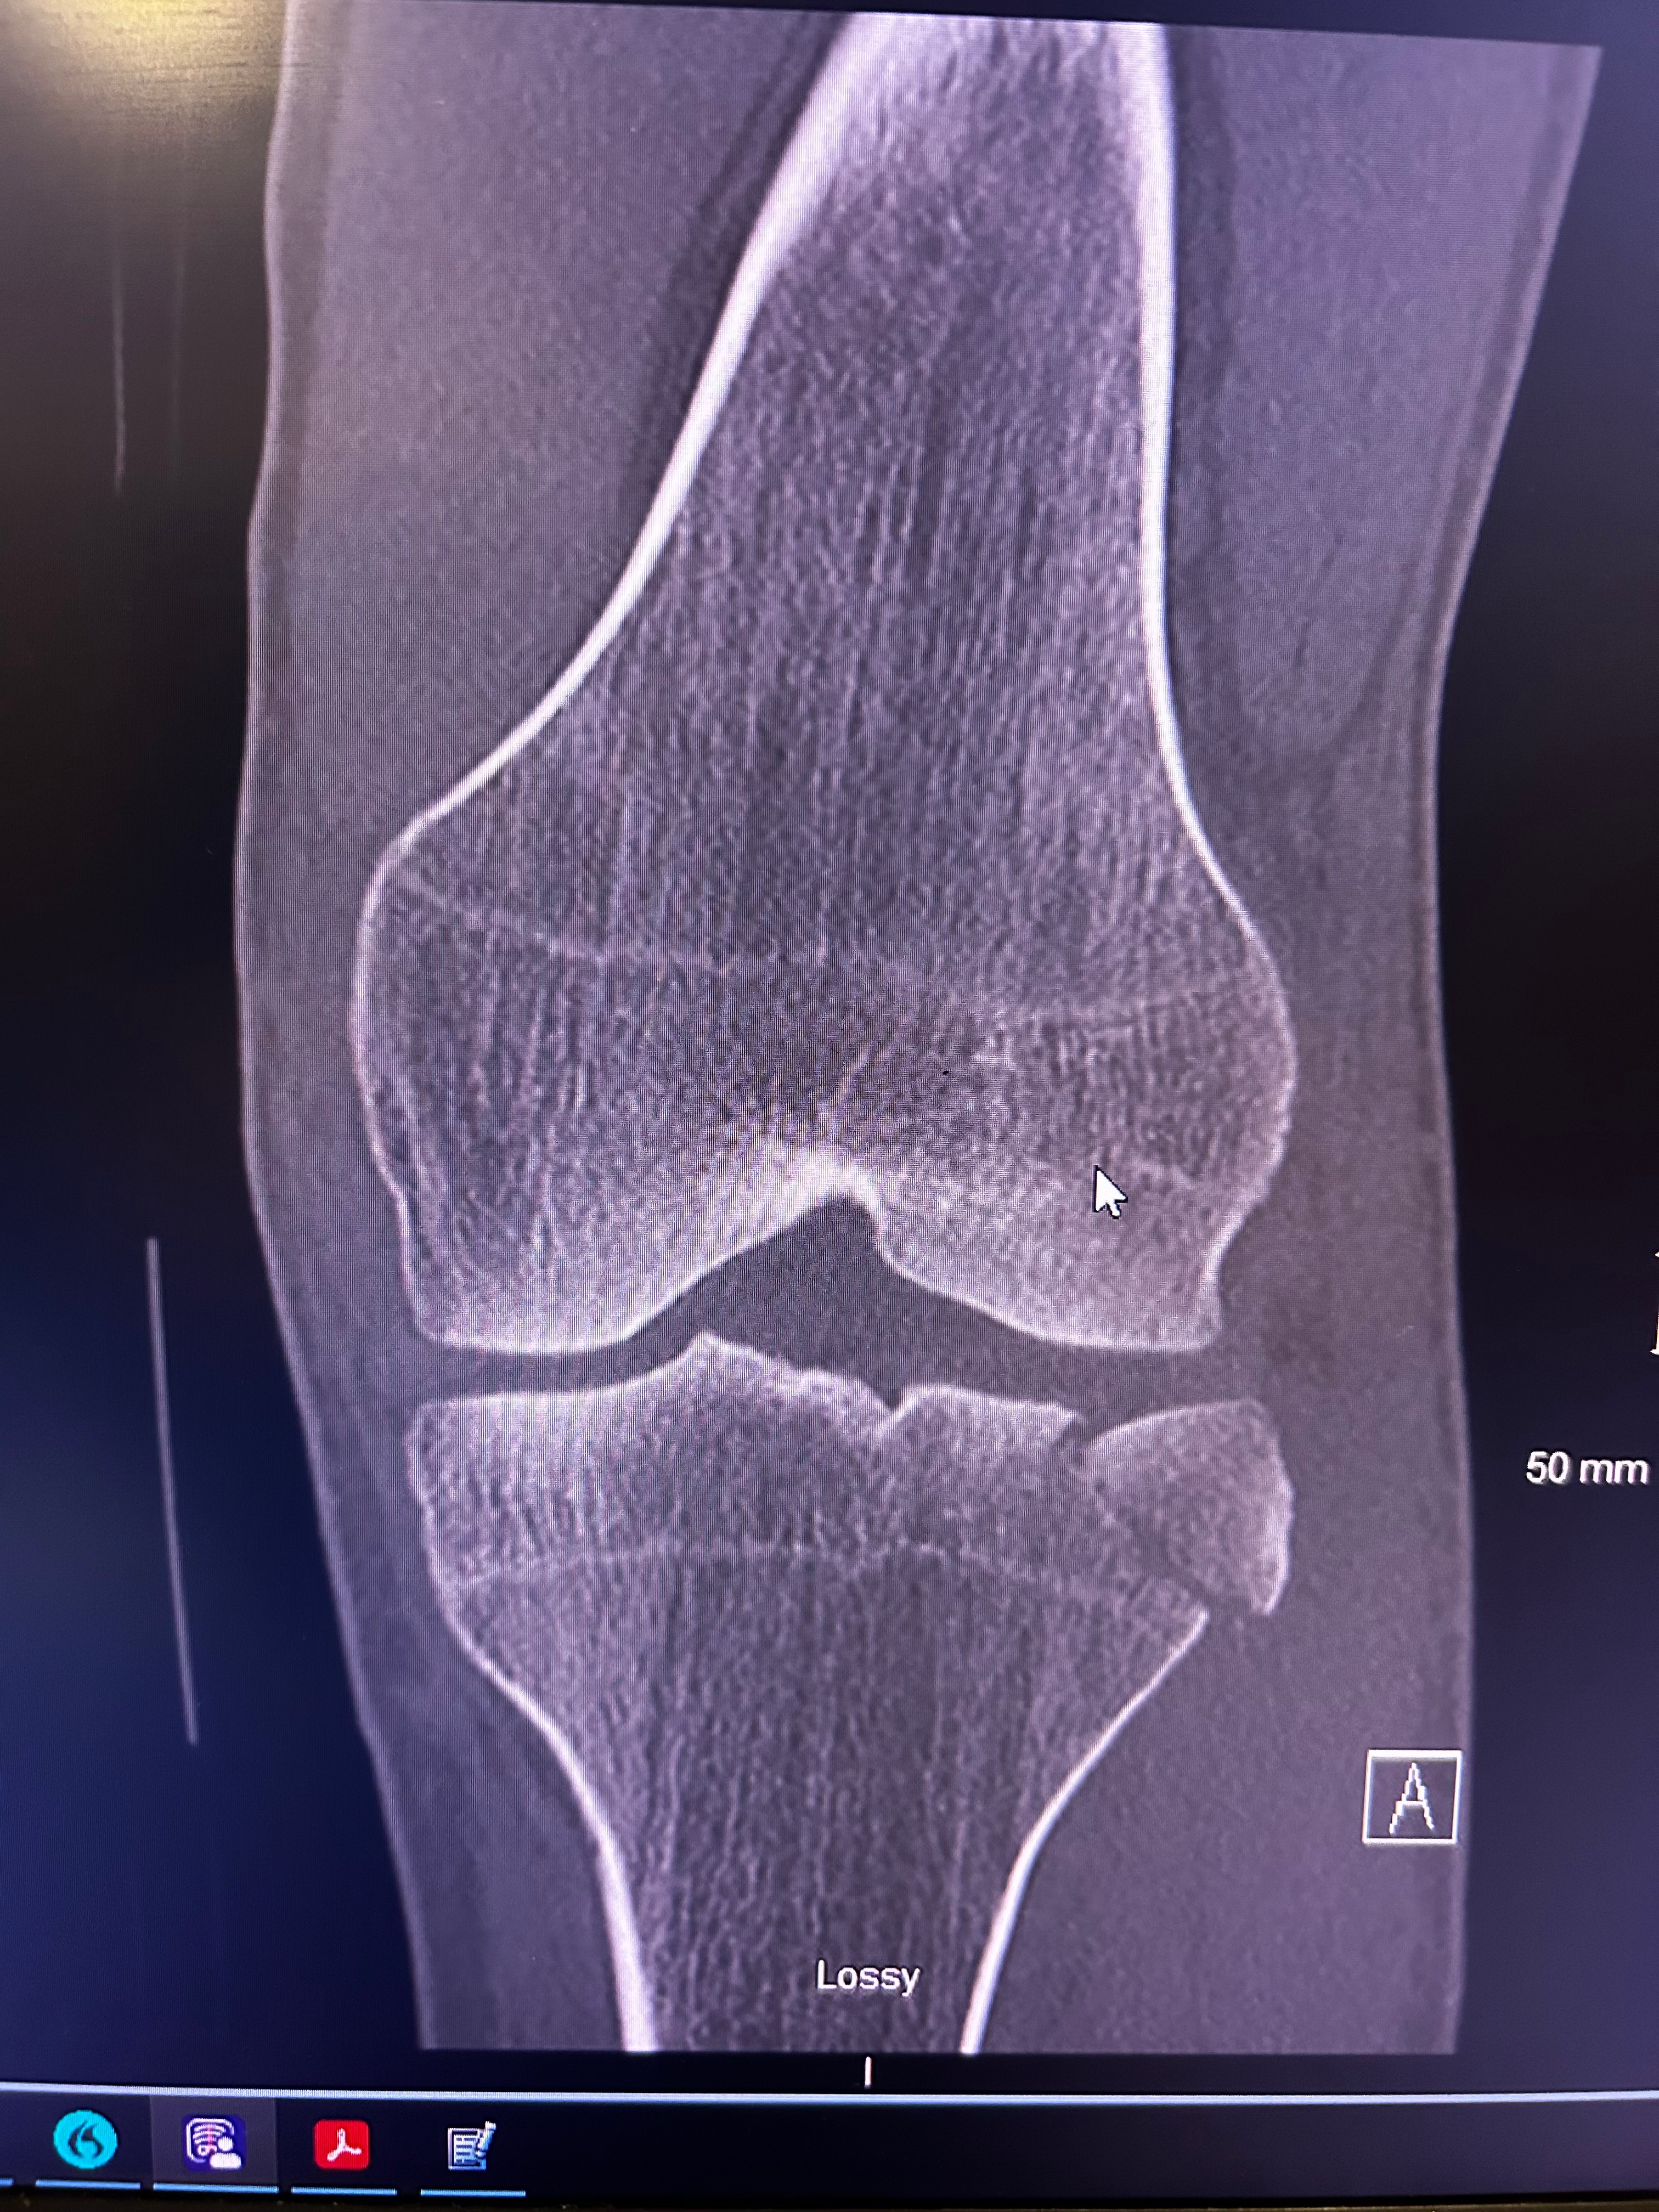

On January 22nd at 10:49 AM, I got the call no one ever wants to receive. It was John, screaming that he had fallen. In that moment, everything stopped. John fell approximately 20–25 feet, causing severe injuries from his left knee down. We are incredibly grateful and beyond blessed that he is alive today, because this situation could have ended very differently.